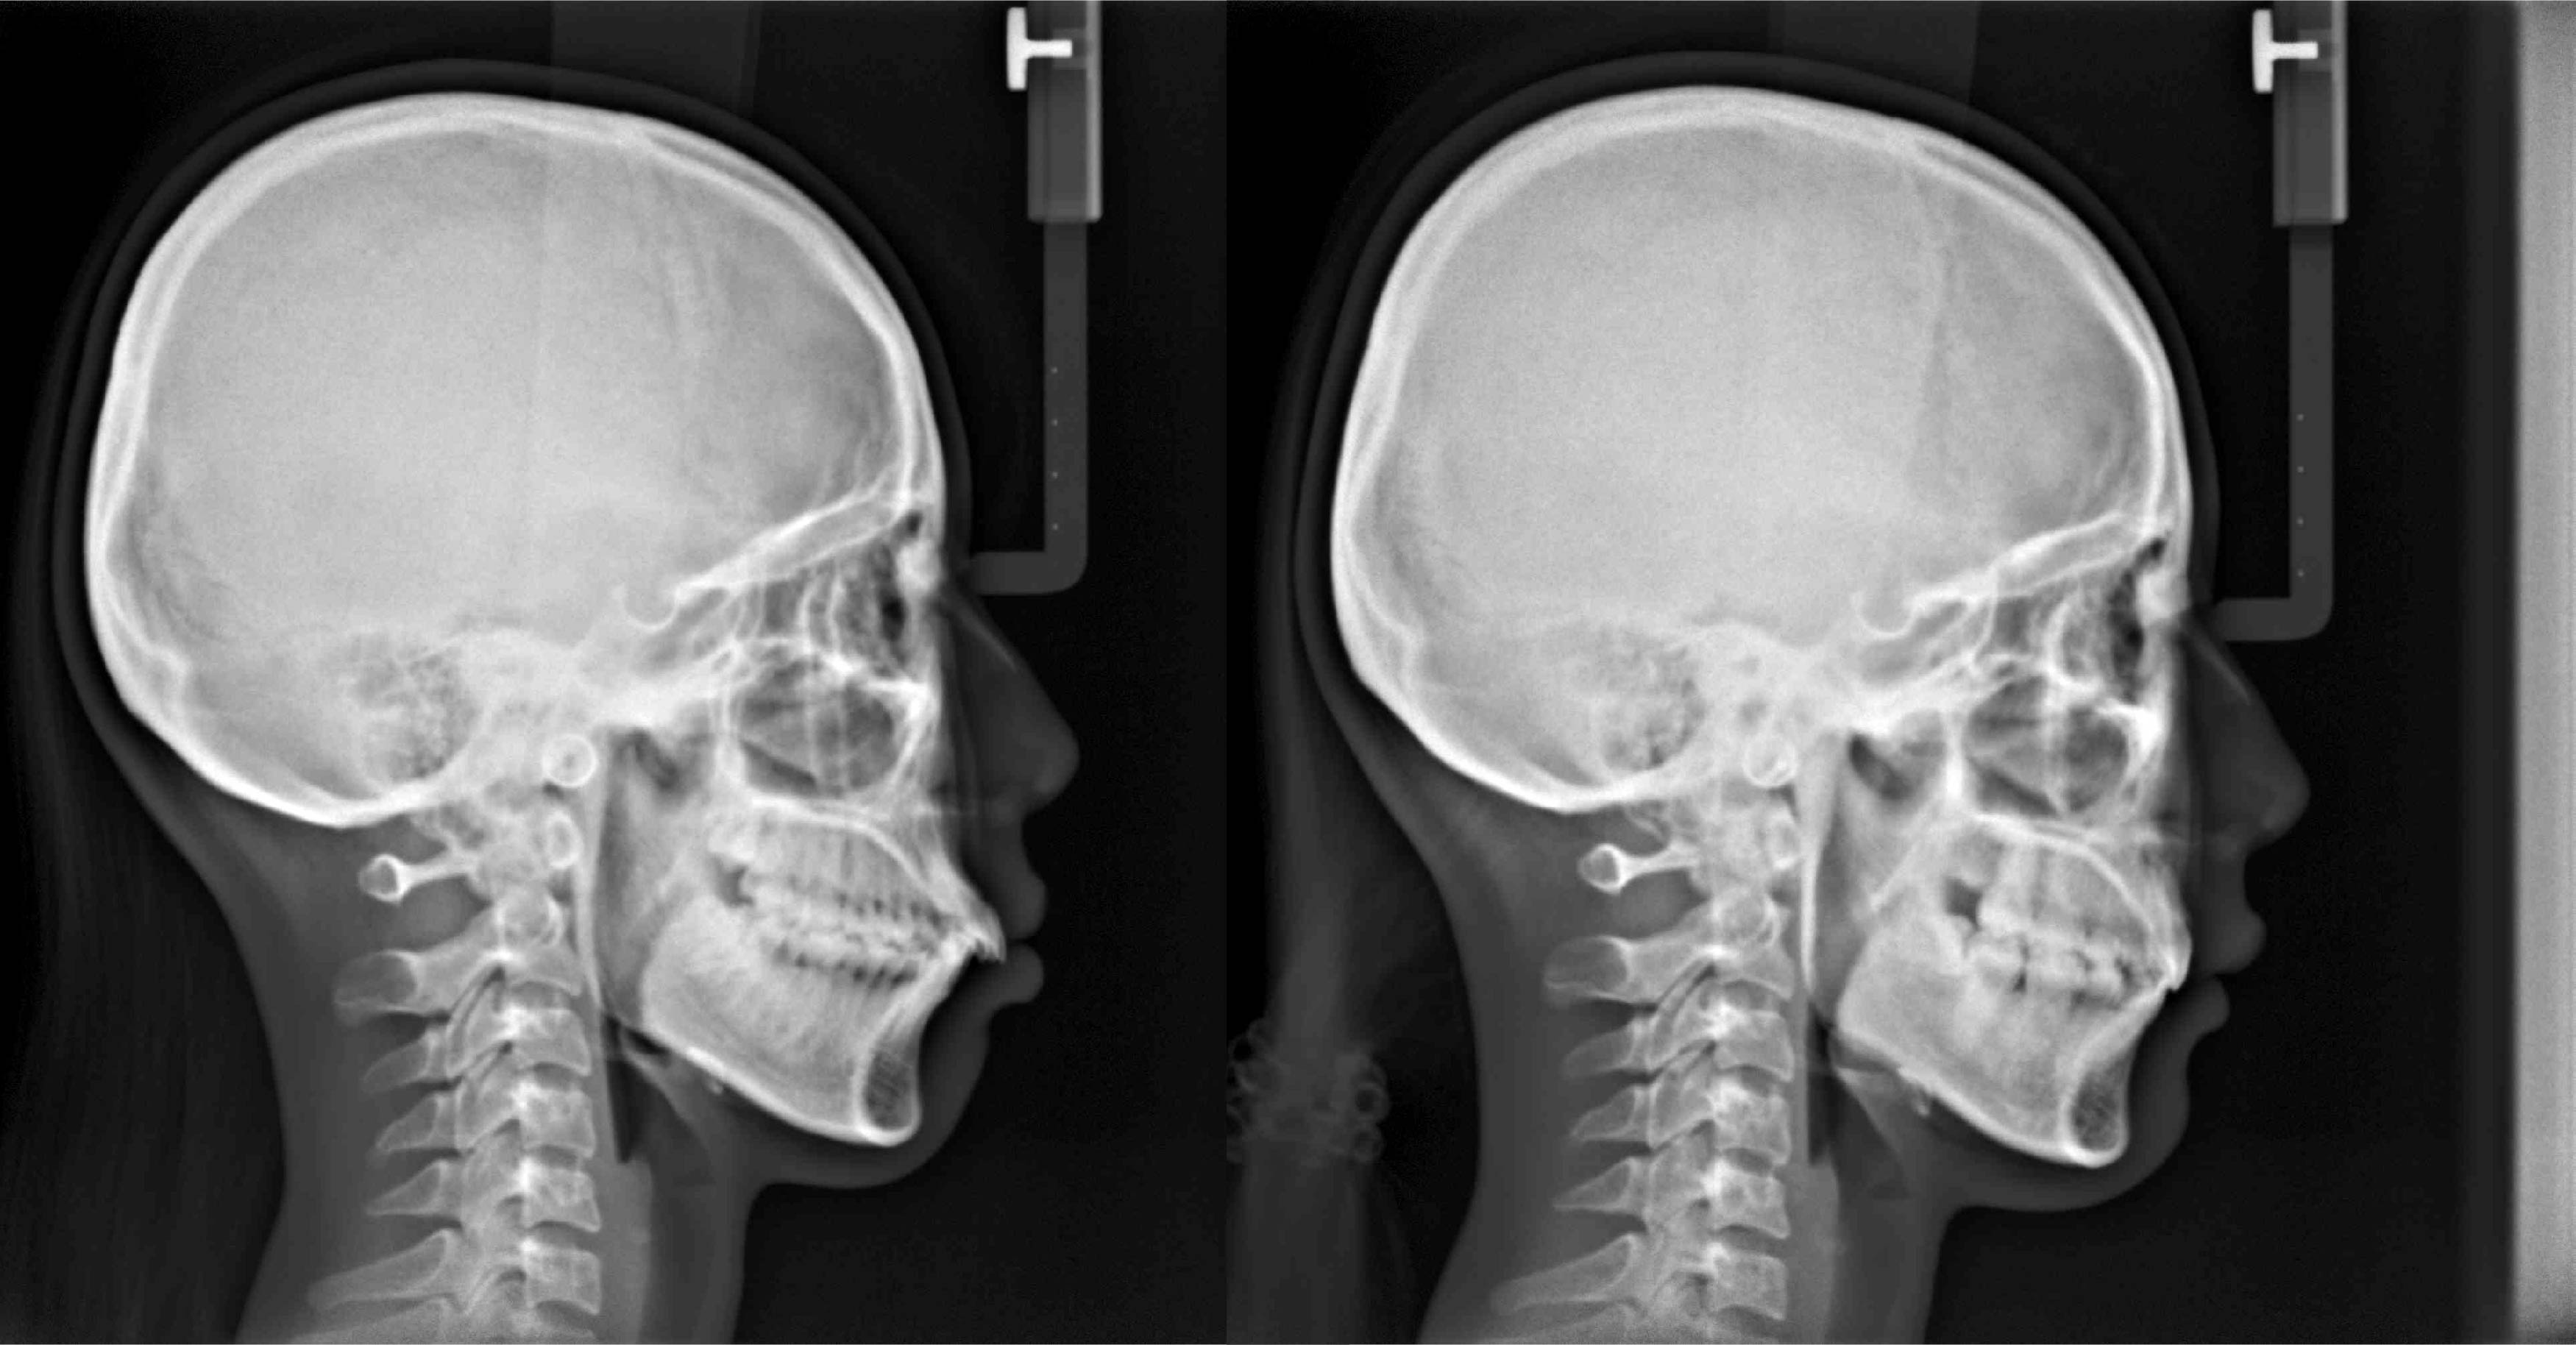

• 青少年早期矯正治療

青少年早期矯正治療

青少年矯正